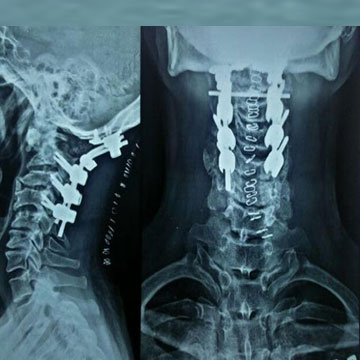

Spinal trauma